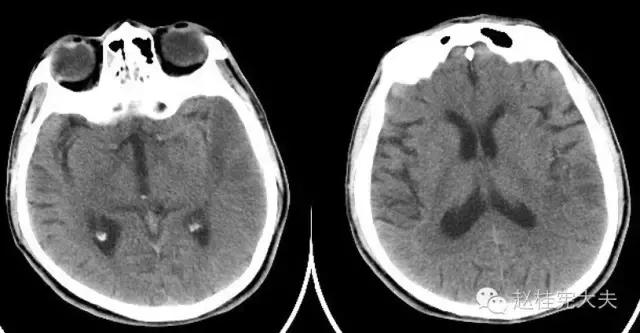

入院前1天的头颅CT:

定位诊断:混合性失语,定位于左侧大脑半球语言中枢(运动和感觉),右侧中枢性面舌瘫,定位于左侧面神经核团以上,右侧上下肢肌力下降,病理征阳性,定位于左侧锥体束。感觉、视野查体无法配合,暂无相应定位考虑。综合考虑,定位于左侧大脑中动脉分布范围。头颅CT:左侧颞叶片状低密度影,左侧大脑中动脉下干支配区,支持临床定位。